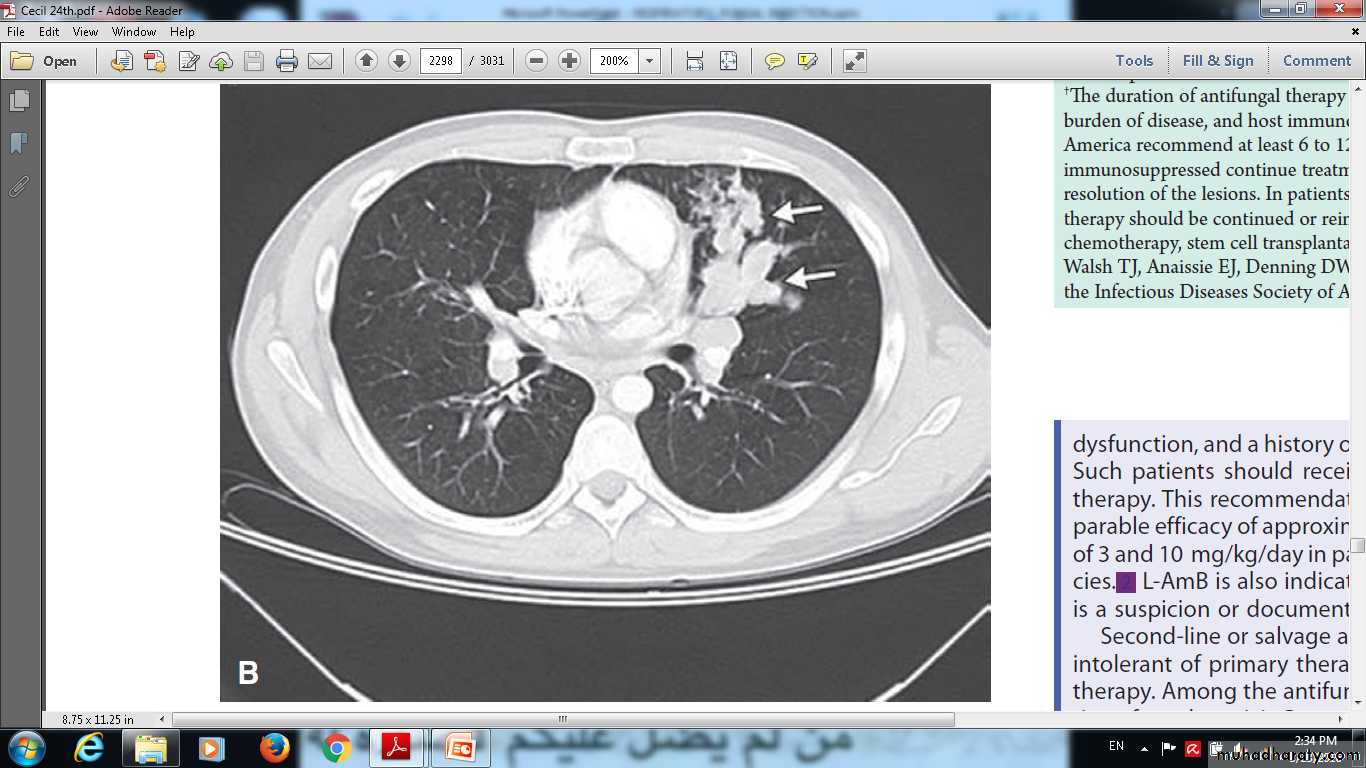

Allergic bronchopulmonary aspergillosis in a patient with a longhistory of asthma. Chest radiographs showed multilobar infiltrates. Computedtomographyshows areas of tubular ( arrows) and cystic ( arrowhead) bronchiectasis.

Allergic bronchopulmonary aspergillosis in a patient with a longhistory of asthma. Chest radiographs showed multilobar infiltrates. Allergic bronchopulmonary aspergillosis in a patient with a longhistory of asthma. Chest radiographs showed multilobar infiltrates predominantlyin the upper lobes, and bilateral mucous plugging ( arrows) with mediastinal and hilar lymphadenopathy